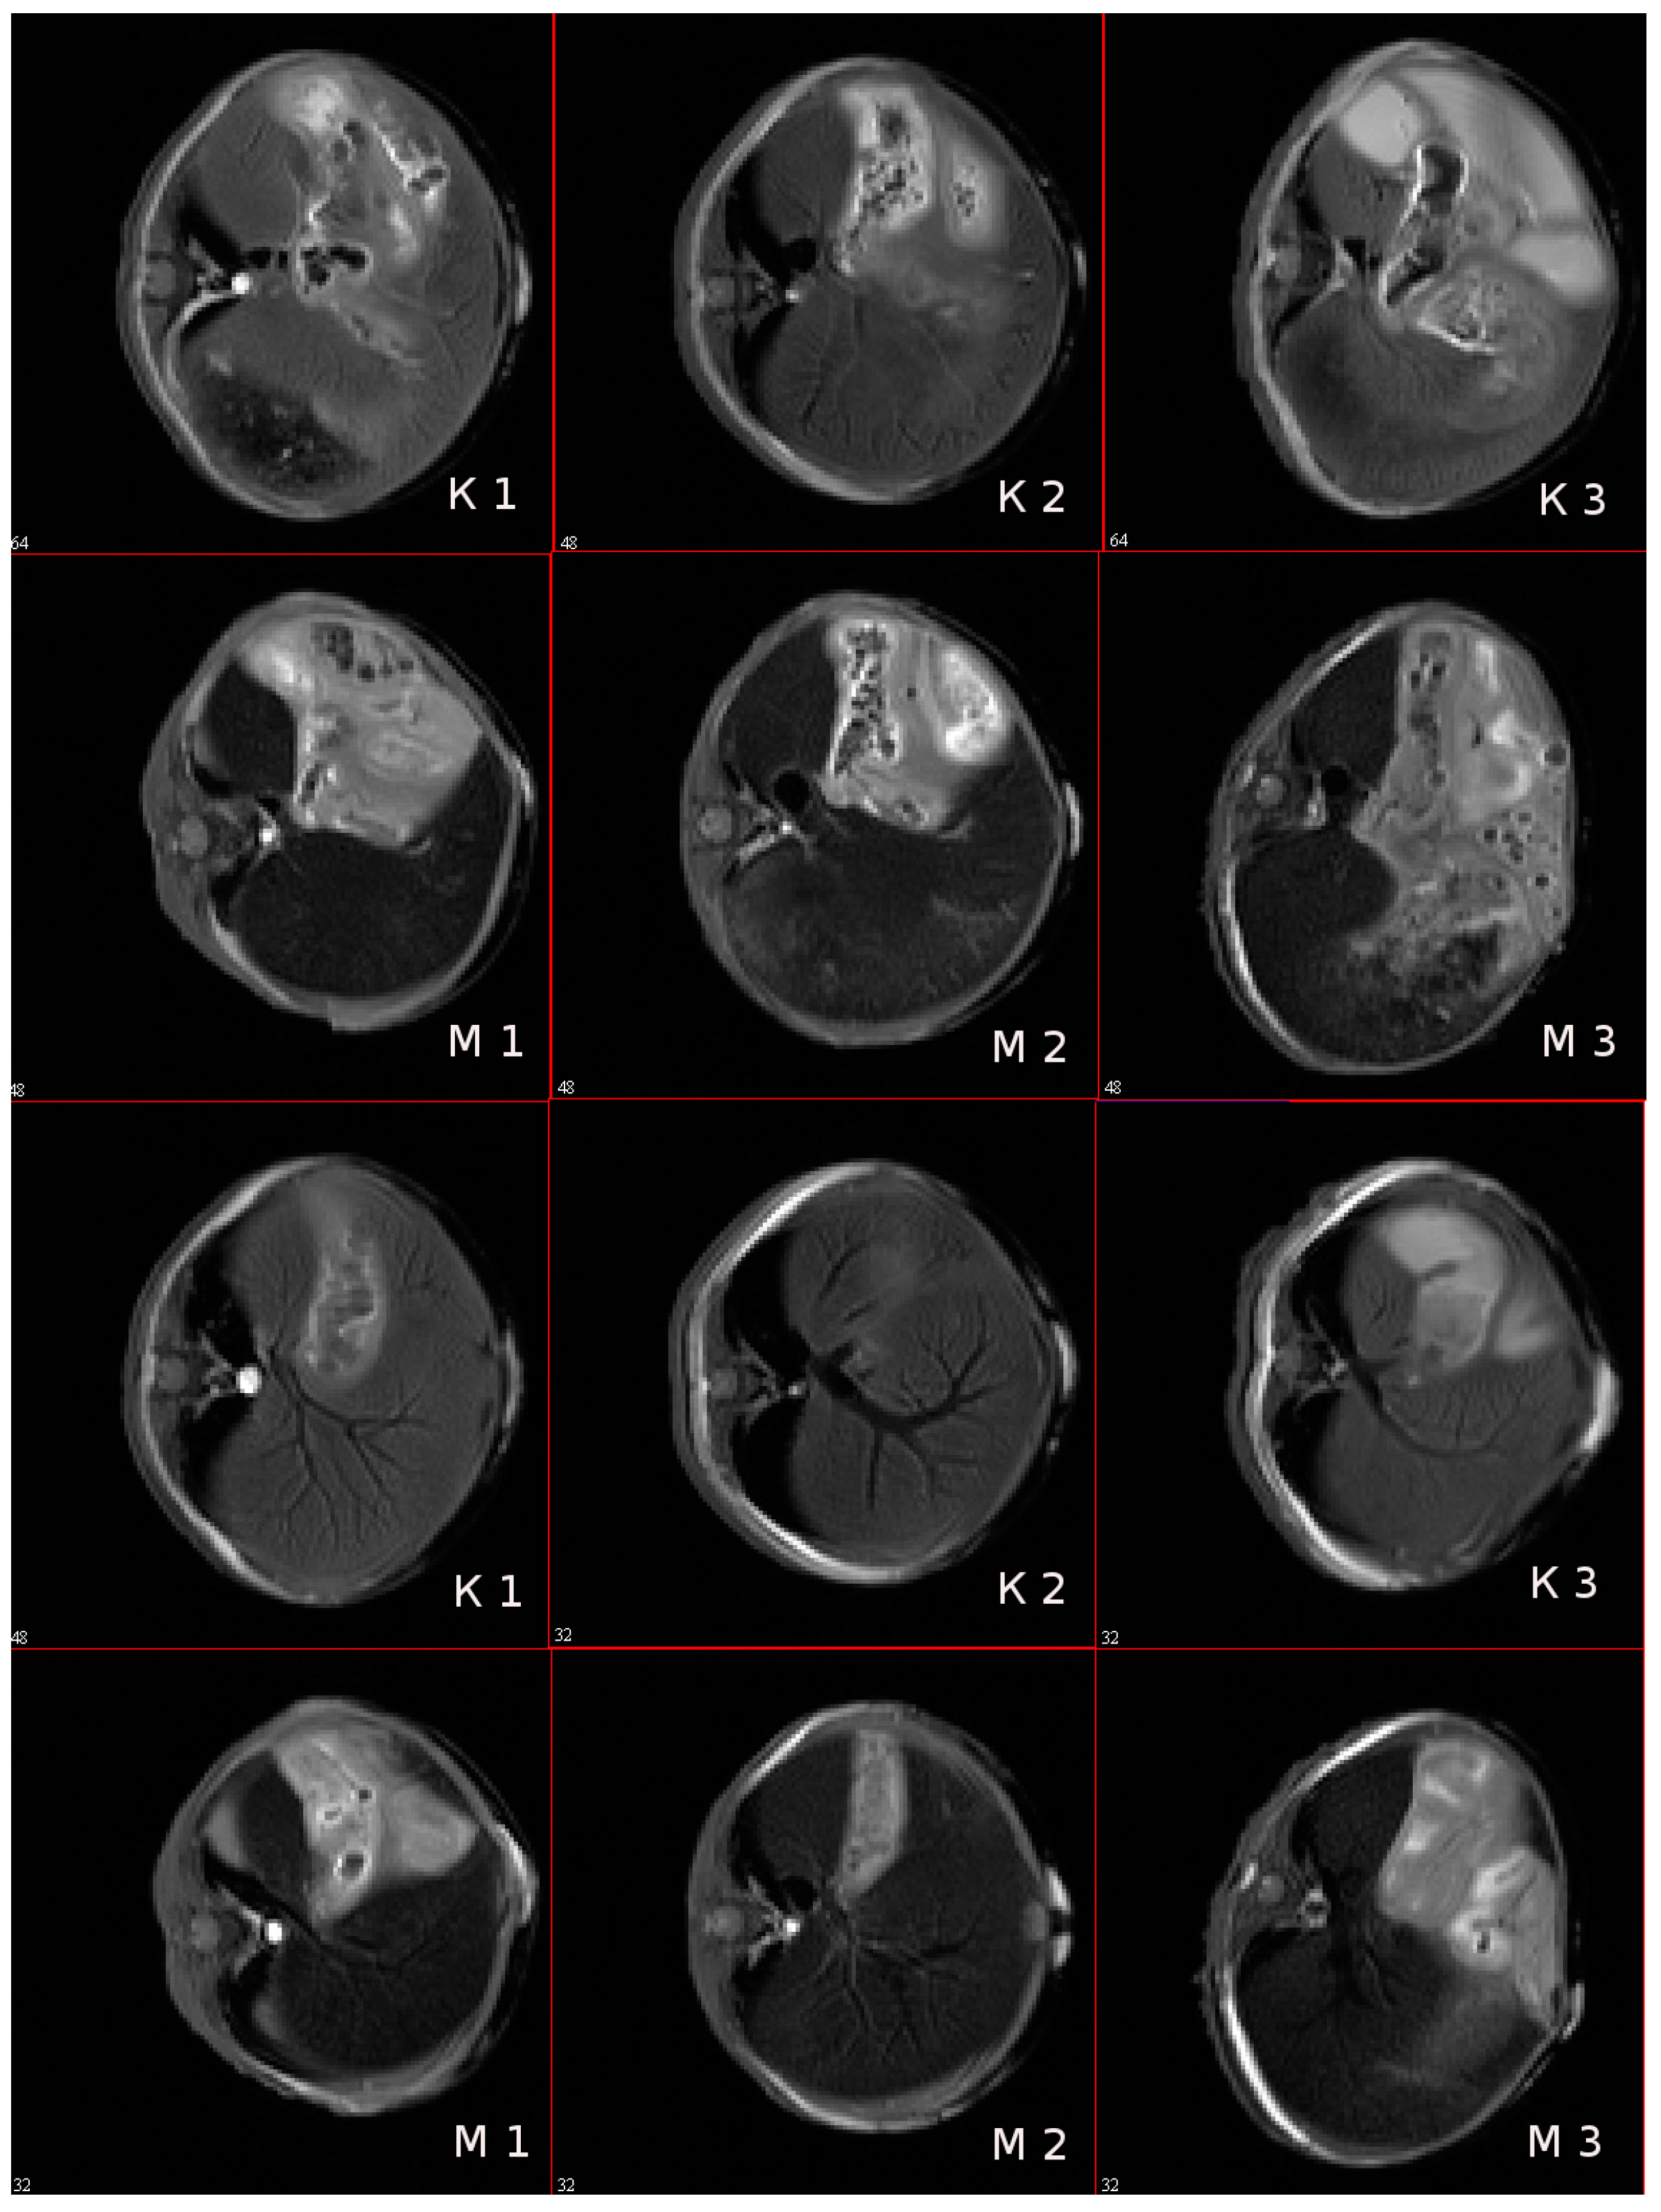

3.9. In Vivo MR-Contrast Enhancing Properties of SPIONs@IFNα-2b Conjugates